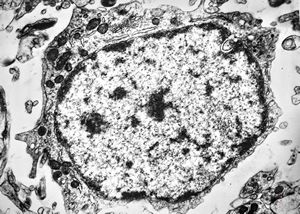

M,10y. | herpetic encephalitis